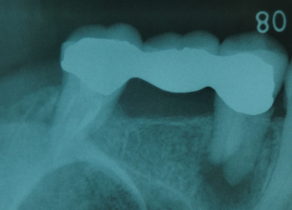

慢性の場合は自覚症状がほとんどなくレントゲン撮影をした時に歯の根っこに黒い影が写ったり、

歯ぐきにニキビのような膿の袋 (フィステル or サイナストラクト) ができて気付くこともあります。